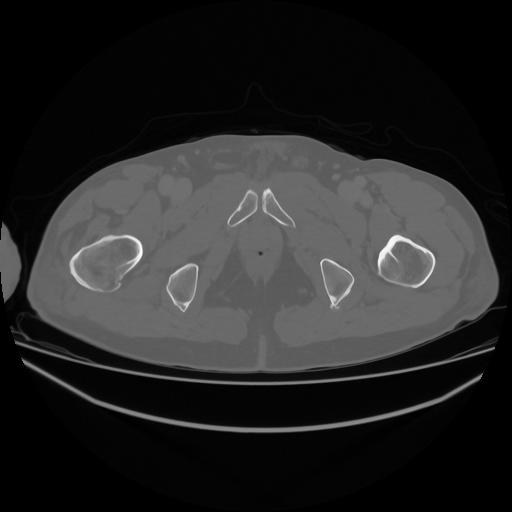

5 CUERPO,CE,Vol,1.0,CUERPO,,